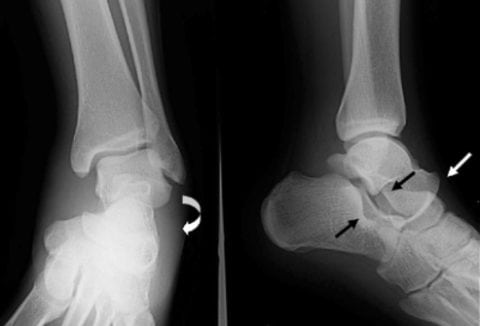

Хруст и щелчки в голеностопных суставах обычно возникают после 50 лет из-за снижения выработки в организме коллагена и эластина, ухудшения кровообращения, замедления регенерации хрящевых тканей. У молодых людей эти звуки появляются редко: обычно после спортивных травм, интенсивных тренировок, тяжелой физической работы. Причины потрескивания суставов во время ходьбы бывают естественными и патологическими. Дифференцировать их самостоятельно в домашних условиях невозможно. После обращения к врачу проводится ряд инструментальных исследований, из которых наиболее информативна рентгенография. Лабораторная диагностика показана при одновременном возникновении хруста, отечности и болезненных ощущений.

- деформирующих артрозов, спровоцированных разрушением гиалиновых хрящей, сопровождающихся формированием костных наростов — остеофитов;

- хондрокальциноза, для которого характерно постепенное накопление в суставной полости кристаллов солей кальция;